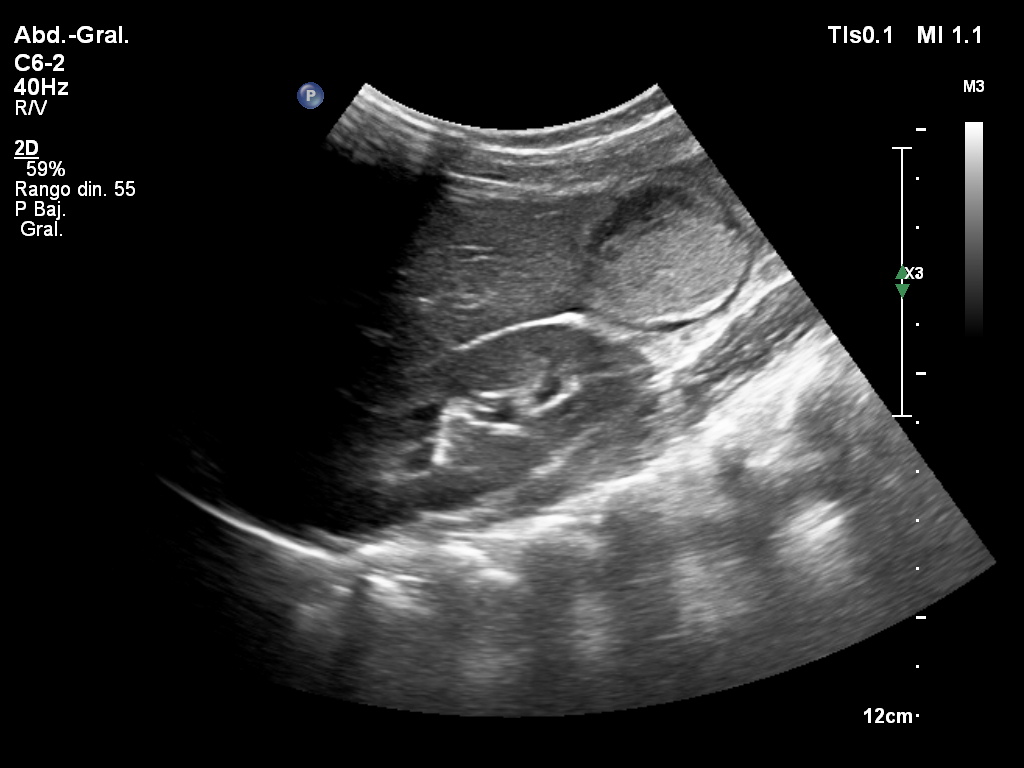

Paciente de 12 años con dolor abdominal. Remitida para estudio de masa intraabdominal.